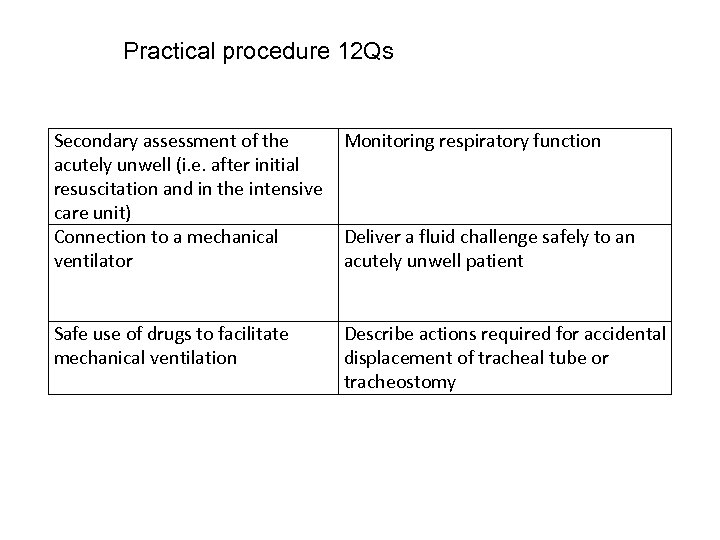

Practical procedure 12 Qs Secondary assessment of the Monitoring respiratory function acutely unwell (i. e. after initial resuscitation and in the intensive care unit) Connection to a mechanical Deliver a fluid challenge safely to an ventilator acutely unwell patient Safe use of drugs to facilitate mechanical ventilation Describe actions required for accidental displacement of tracheal tube or tracheostomy